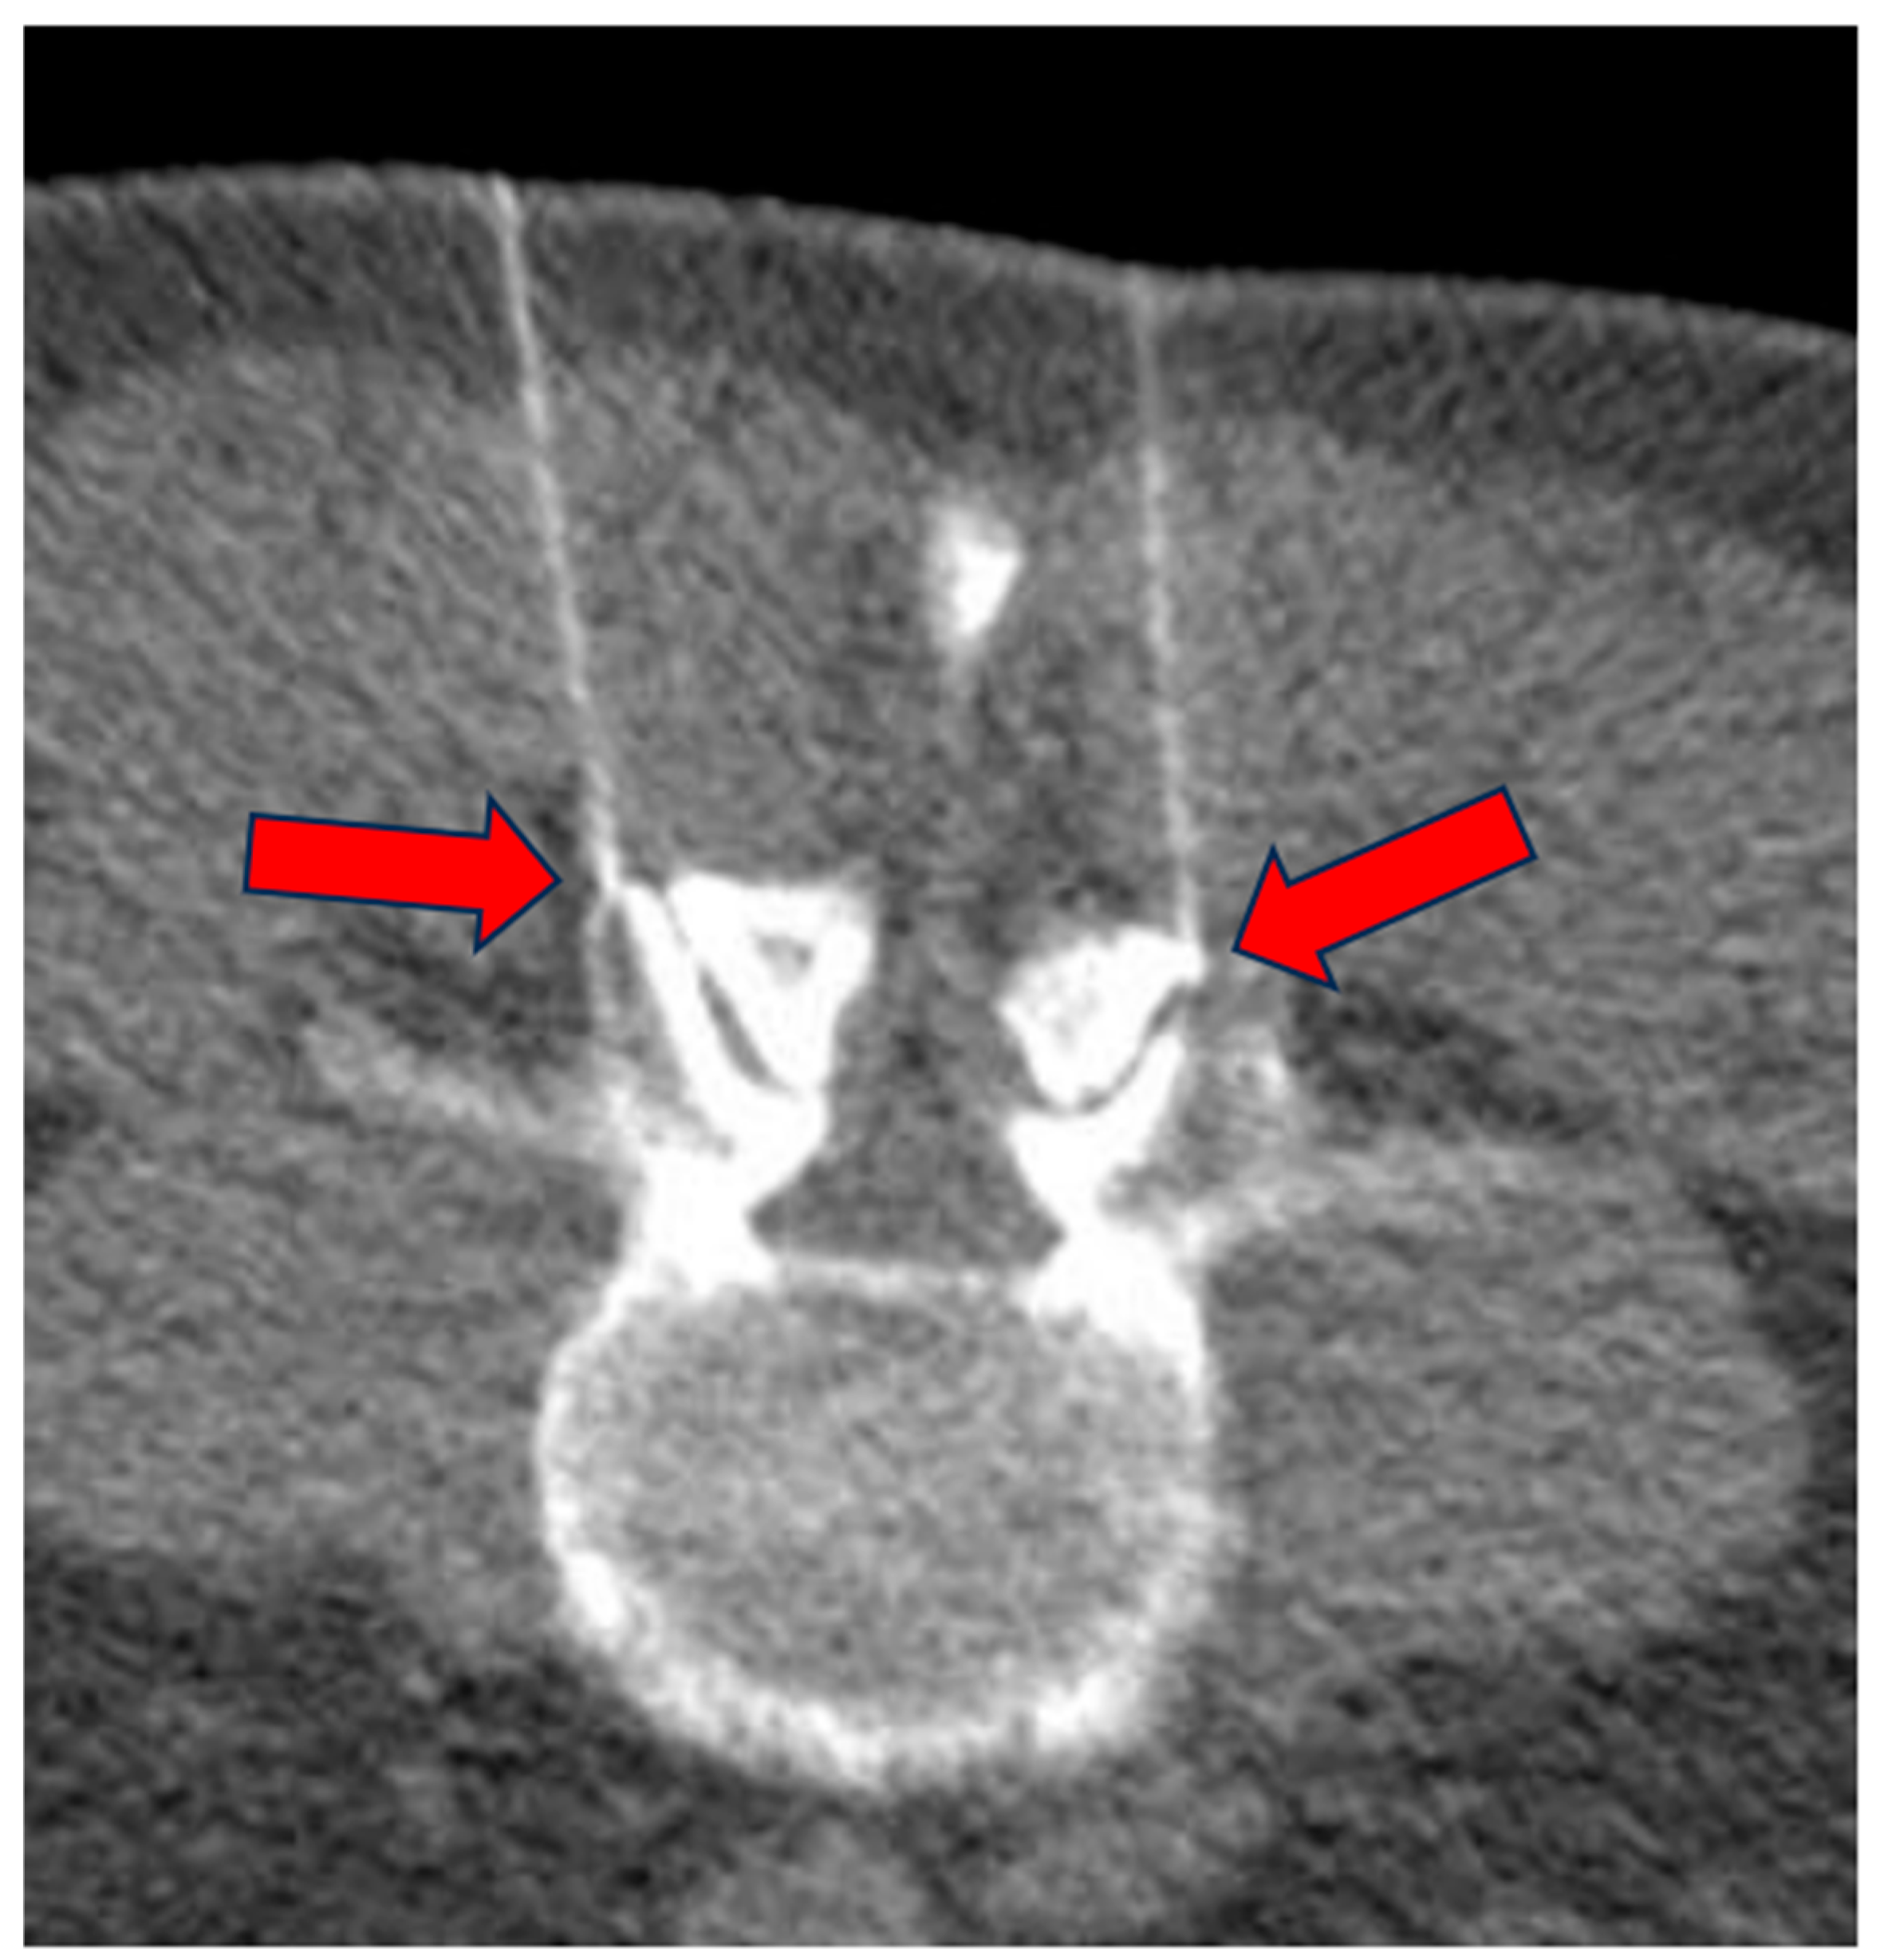

Figure 4.

Low-dose CT scan for correct positioning of the needles at the facet joint level (arrows).